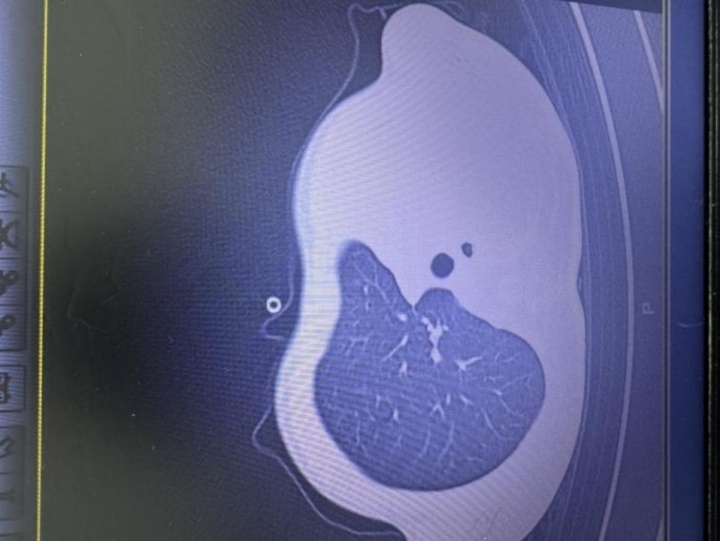

急诊检查结果让医护人员瞬间紧张:验血显示炎症指标大幅上升,胸片更发现左侧肺叶几乎“不工作了,影像学中变成大片白色,即通常所说的“白肺”,意味着肺功能严重受损,孩子已经缺氧,随时有窒息危险。

图:影像显示肺白了一半